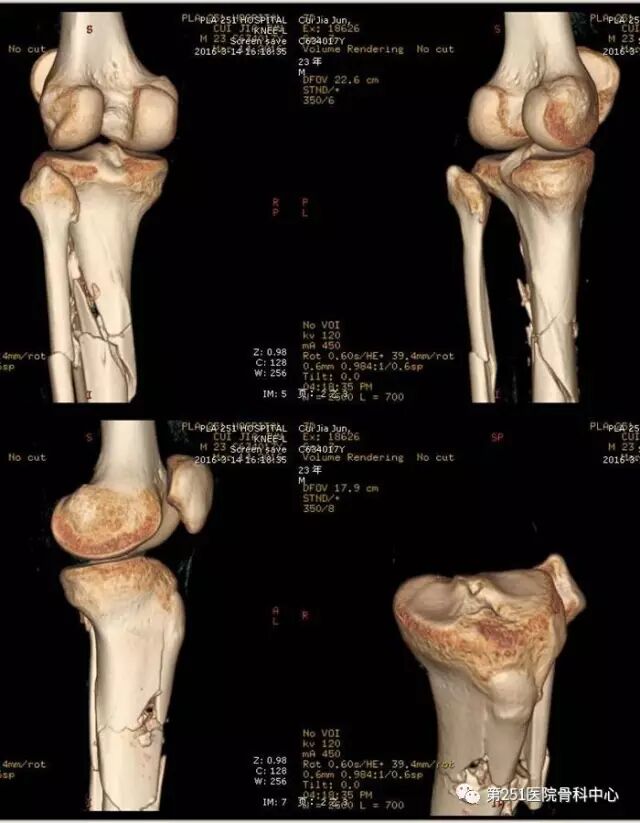

病例6:男性,39岁,车祸伤SchatzkerⅥ型胫骨平台骨折。

![]()